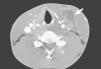

Medicina Clínica Tuberculosis ganglionar en paciente con masa cervical indolora

Tuberculosis ganglionar en paciente con masa cervical indolora

Lymph node tuberculosis in a patient with a painless cervical mass